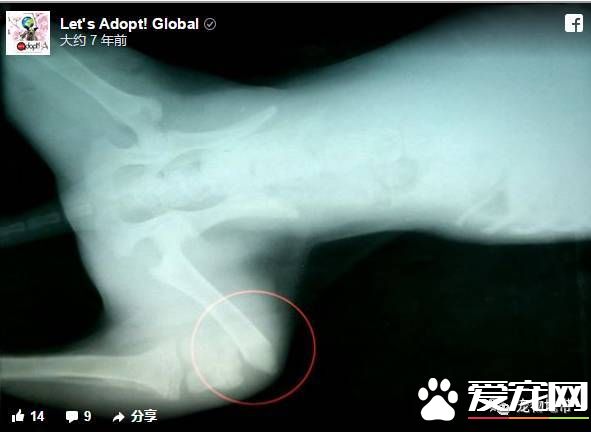

森科和伙伴庆幸自己及时发现了它,否则这只狗宝宝将躺在呼啸而过的汽车中间,孤独地饿死或者冻死。 兽医检查的结果 森科和伙伴把狗宝宝送到兽医的诊所检查,兽医给狗宝宝拍X光照片发现,它有两条腿完全断了,这是狗狗为什么不会跑动的原因。

兽医推测,狗宝宝应该是一只流浪狗,无意中跑到高速路上被汽车撞伤。肇事汽车司机或许并没有意识到撞了一只狗狗,或许知道撞了狗狗却没当作一回事,所以没有停车就保持高速行驶地离开了。 感到鼻酸的兽医和动物救护志工,对狗宝宝细心诊治、看护,希望它能够恢复健康。 狗宝宝恢复健康 经过手术之后,狗宝宝被送到寄养家庭休养治疗。这户人家还有其它狗狗,狗狗们在一起总是很快乐。此外,这户人家还有猫咪。因为从小跟狗狗一起成长,这家人的猫咪跟狗狗相处融洽。 尽管狗宝宝暂时无法跑动行走,但它得到了悉心地看护,结交了新的狗朋友、猫伙伴。